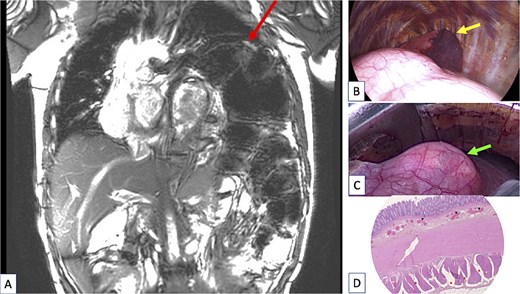

(A) Coronal view of the chest magnetic resonance imaging done after sigmoidectomy showing a huge persistent left diaphragmatic eventration (arrow at the top of figure) containing the remaining large megacolon. The left lung was totally compressed in the upper part of the pleural cavity and a severe mediastinal shift persisted despite digestive surgery. (B) Peroperative view of the thoracic procedure showing the major diaphragm eventration pushing the lung (arrow showing lung) in the upper part the pleural cavity. The lung is almost in full atelectasis. (C) Peroperative view of the thoracic procedure showing a “transparent diaphragm” (arrow showing thin diaphragm) without muscle consistence. (D) Histopathologic examination of the resected colon, using haematoxylin and eosin (H&E) staining. Cross section of the colonic wall (H&E—2.5×) showing small congestive vessels within the submucosal layer (black triangles) and fibrosis dissociating the external muscular layer (red triangles).